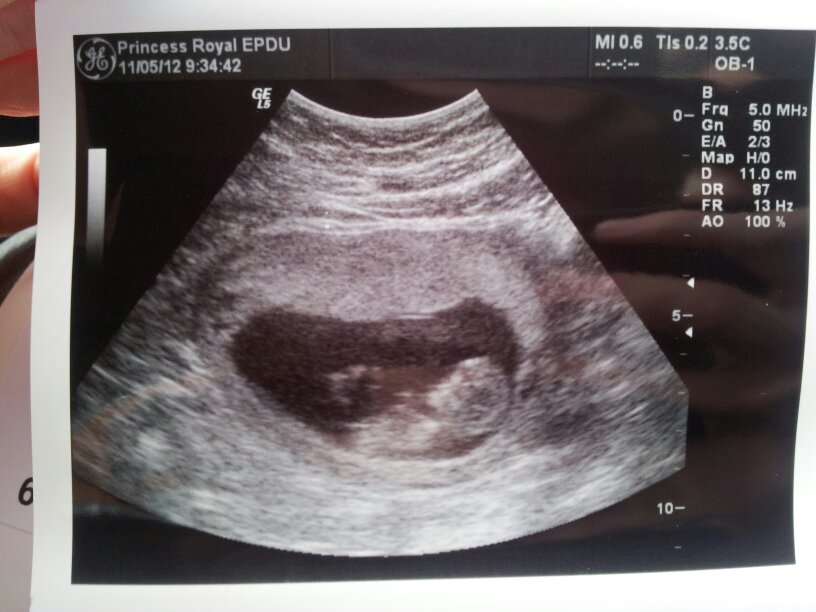

I would say 85% girl. If the nub was pictured a bit clearer and you were a tiny bit further ahead, I would go even higher, but because picture is not perfect and you were just over the 12 week mark, I would stick with 85% chance of a girl. Hope this helps x

Here is my 11 week scan I think the nub is clear on there.